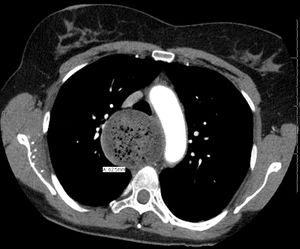

من الأعراض الأخرى الأقل شيوعا قلس الطعام غير المهضوم ونقص الوزن وحرقة الفؤاد والألم الصدري. قد يؤدي قلس المواد الطعامية إلى السبيل التنفسي أثناء الاستلقاء ليلا إلى حدوث الاختناق أو ذات الرئة الشفطية (ذات الرئة بالارتشاف). غالبا ما يكون نقص الوزن خفيفا ما بين 5 إلى 10 كغ. يمكن أن يكون سبب حس حرقة الفؤاد لدى بعض المرضى هو وجود داء الجزر المعدي المريئي مستبطنا لديهم، وقد يكون بسبب التخريش المباشر للمواد الطعامية ومستقلباتها المحصورة في المريء. قد يكون الألم الصدري هو العرض الذي يراجع به بعض المرضى بشكل مشابه للألم القلبي. يذكر أيضا أن بعض المرضى الذين يراجعون الطبيب بما يعرف باللقمة الهستيرية يعانون من من تعذر الارتخاء المريئي.[2][4][5]